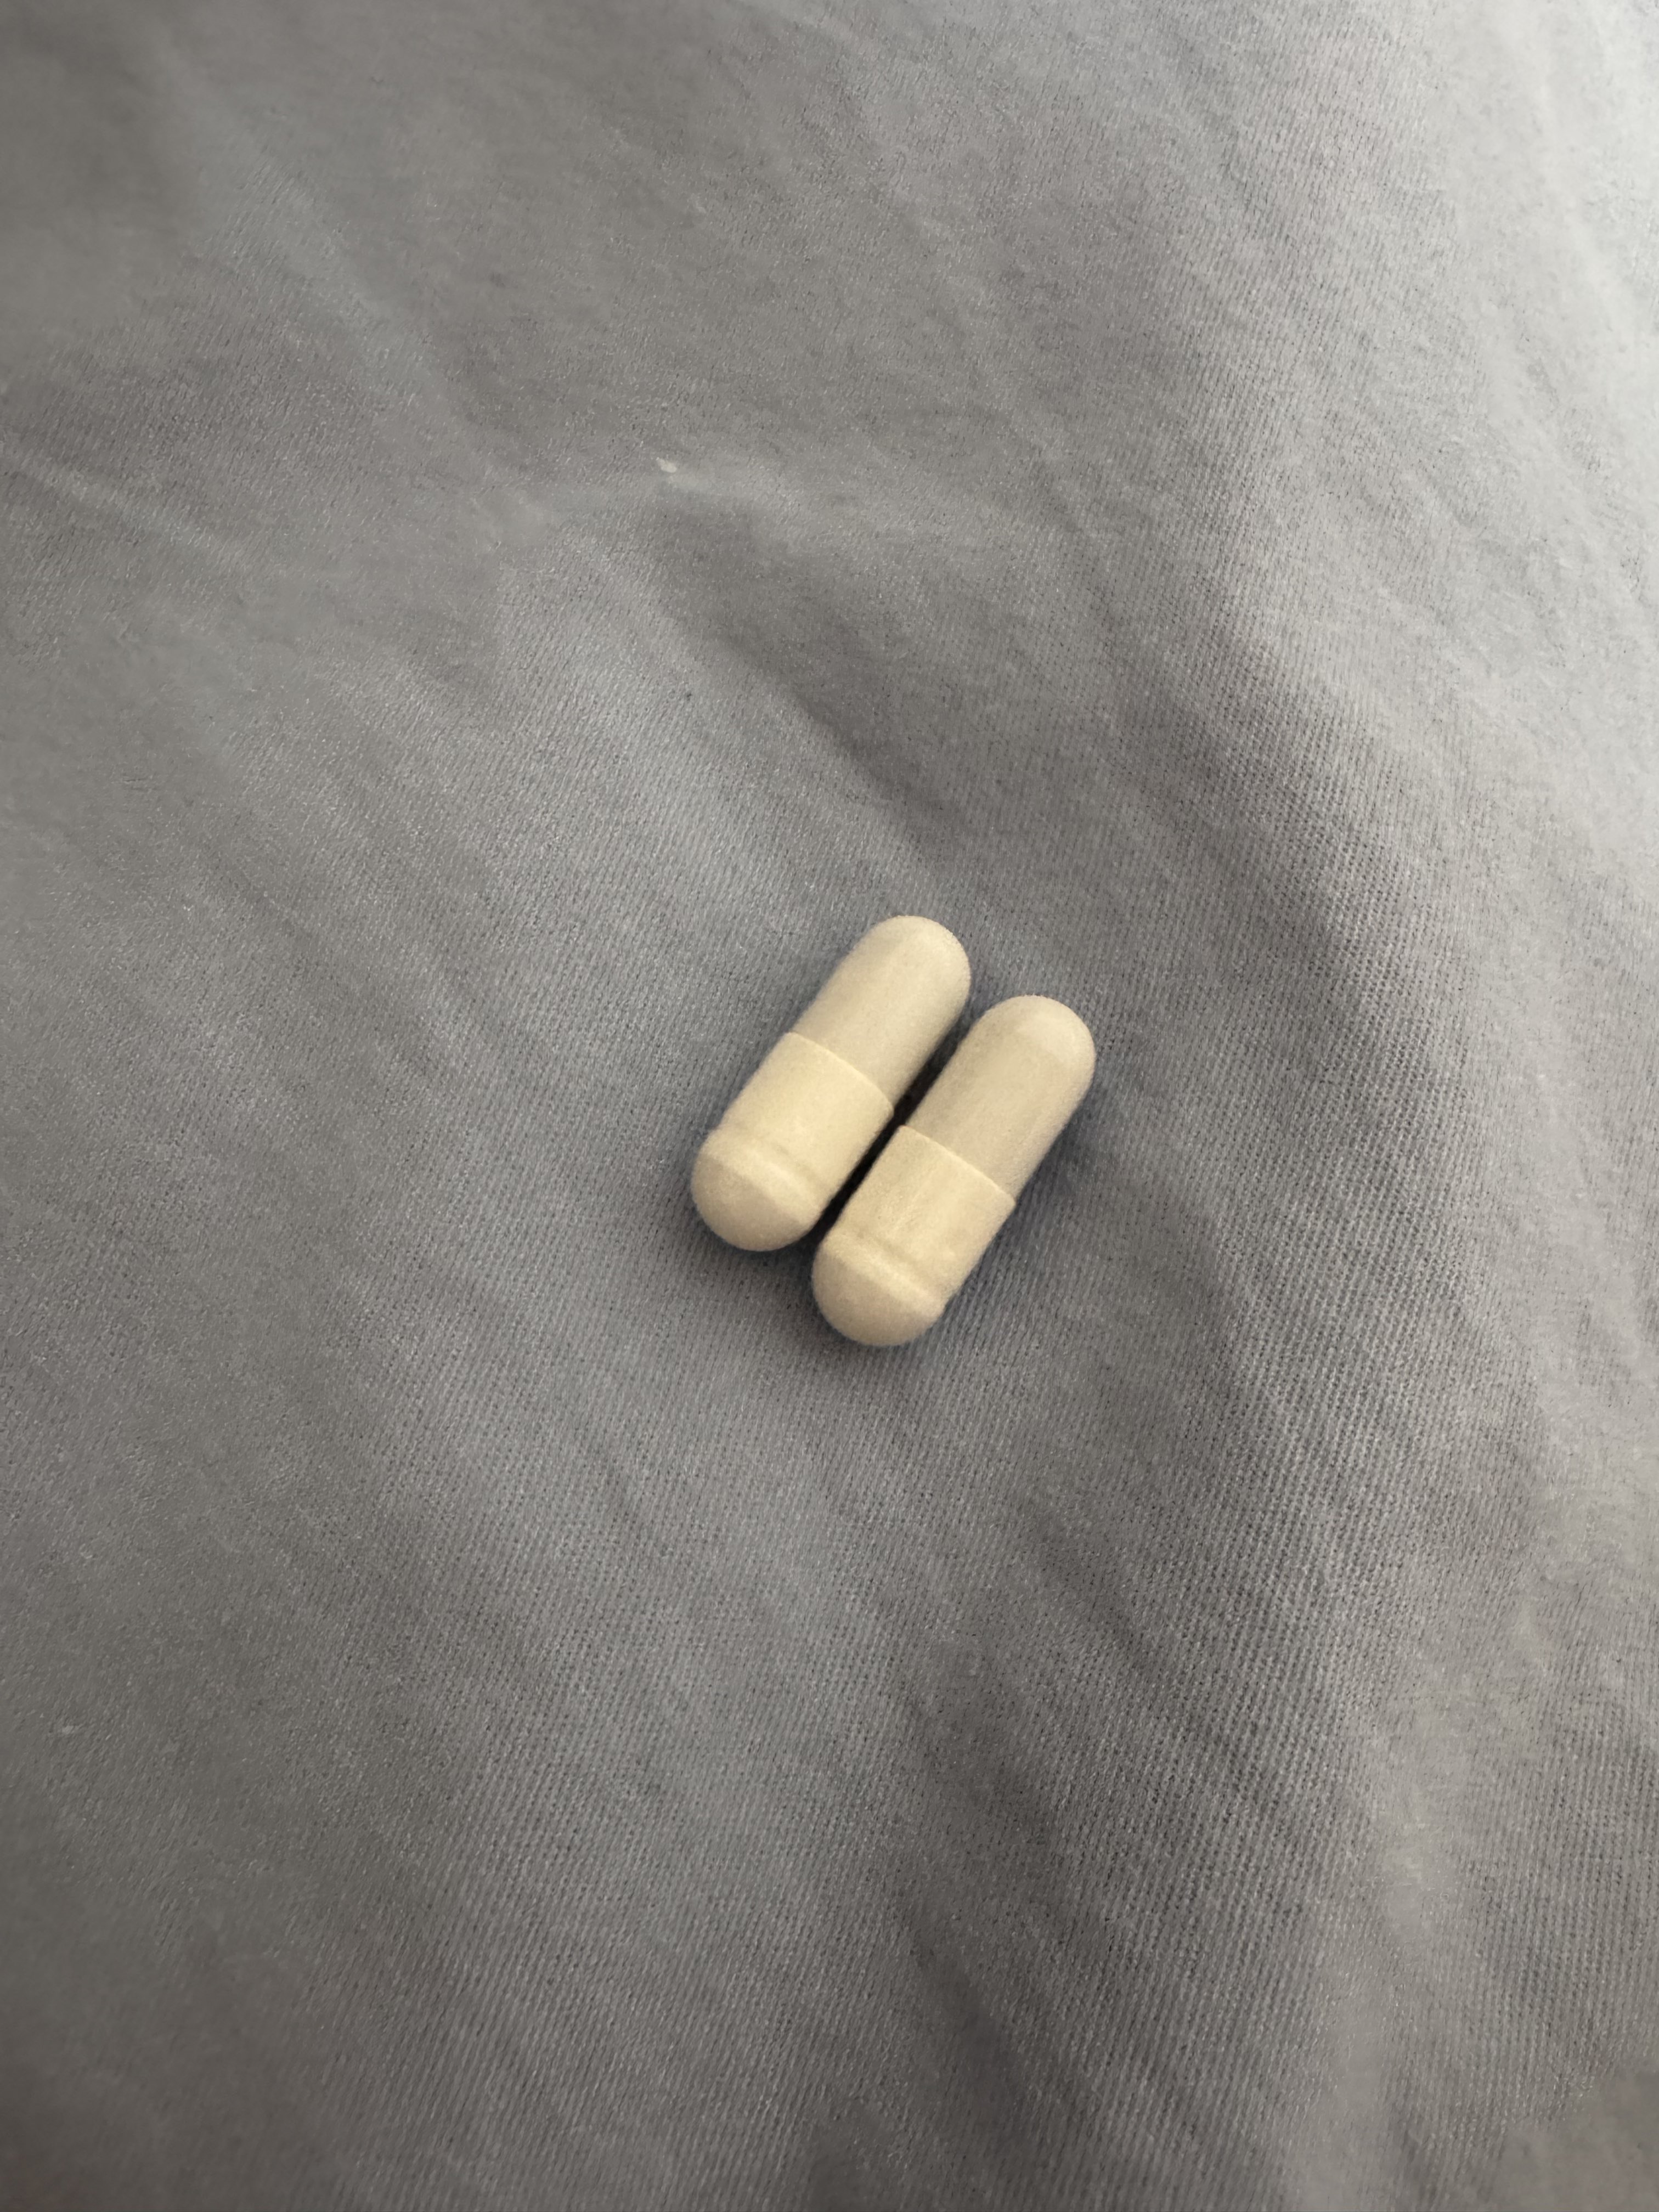

一些白兔27t的体验:

显著的梦境增强,几乎是半梦半醒的状态(或许是咖啡因导致的?),会梦到很多开心的事态发展并相信那就是事实,虽然在6h的睡眠后醒来不记得内容了(好希望能记住)

没有服用会干扰酶的药物或食物。

睡眠期间心率和血氧的数据比平时低一些。总之没有发生什么很特别的事。 https://t.co/PAXqkakGGo